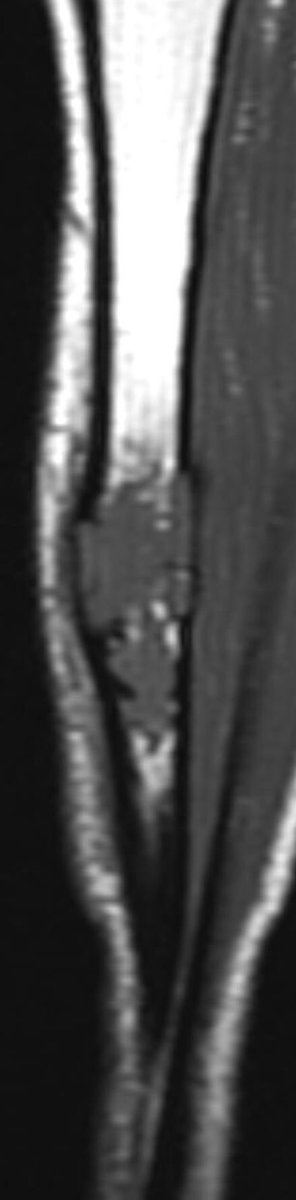

MRI is mandatory for accurate local staging (intramedullary extent, multifocal tibial and fibular disease and extra-osseous extension) and surgical planning. AD is typically isointense / mildly hyperintense to muscle on T1 weighted images

similar to fat on fast spin-echo T2 and hyperintense on inversion recovery and fluid-sensitive fat saturated sequences. The tumour enhances intensely and homogeneously.

The tumour in the current case appeared to have arisen in the anterior cortex, extending inferiorly into both cortex and medulla, as a single focus of disease. The trabeculated appearance on radiographs appears to reflect the unusual extension of tumour through tibial cortex.

, with preservation of vertical ridges of cortical bone, surrounded by tumour, adjacent to areas of marked cortical thinning. Oedema-like hyperintensity on the bone surface suggests imminent fracture